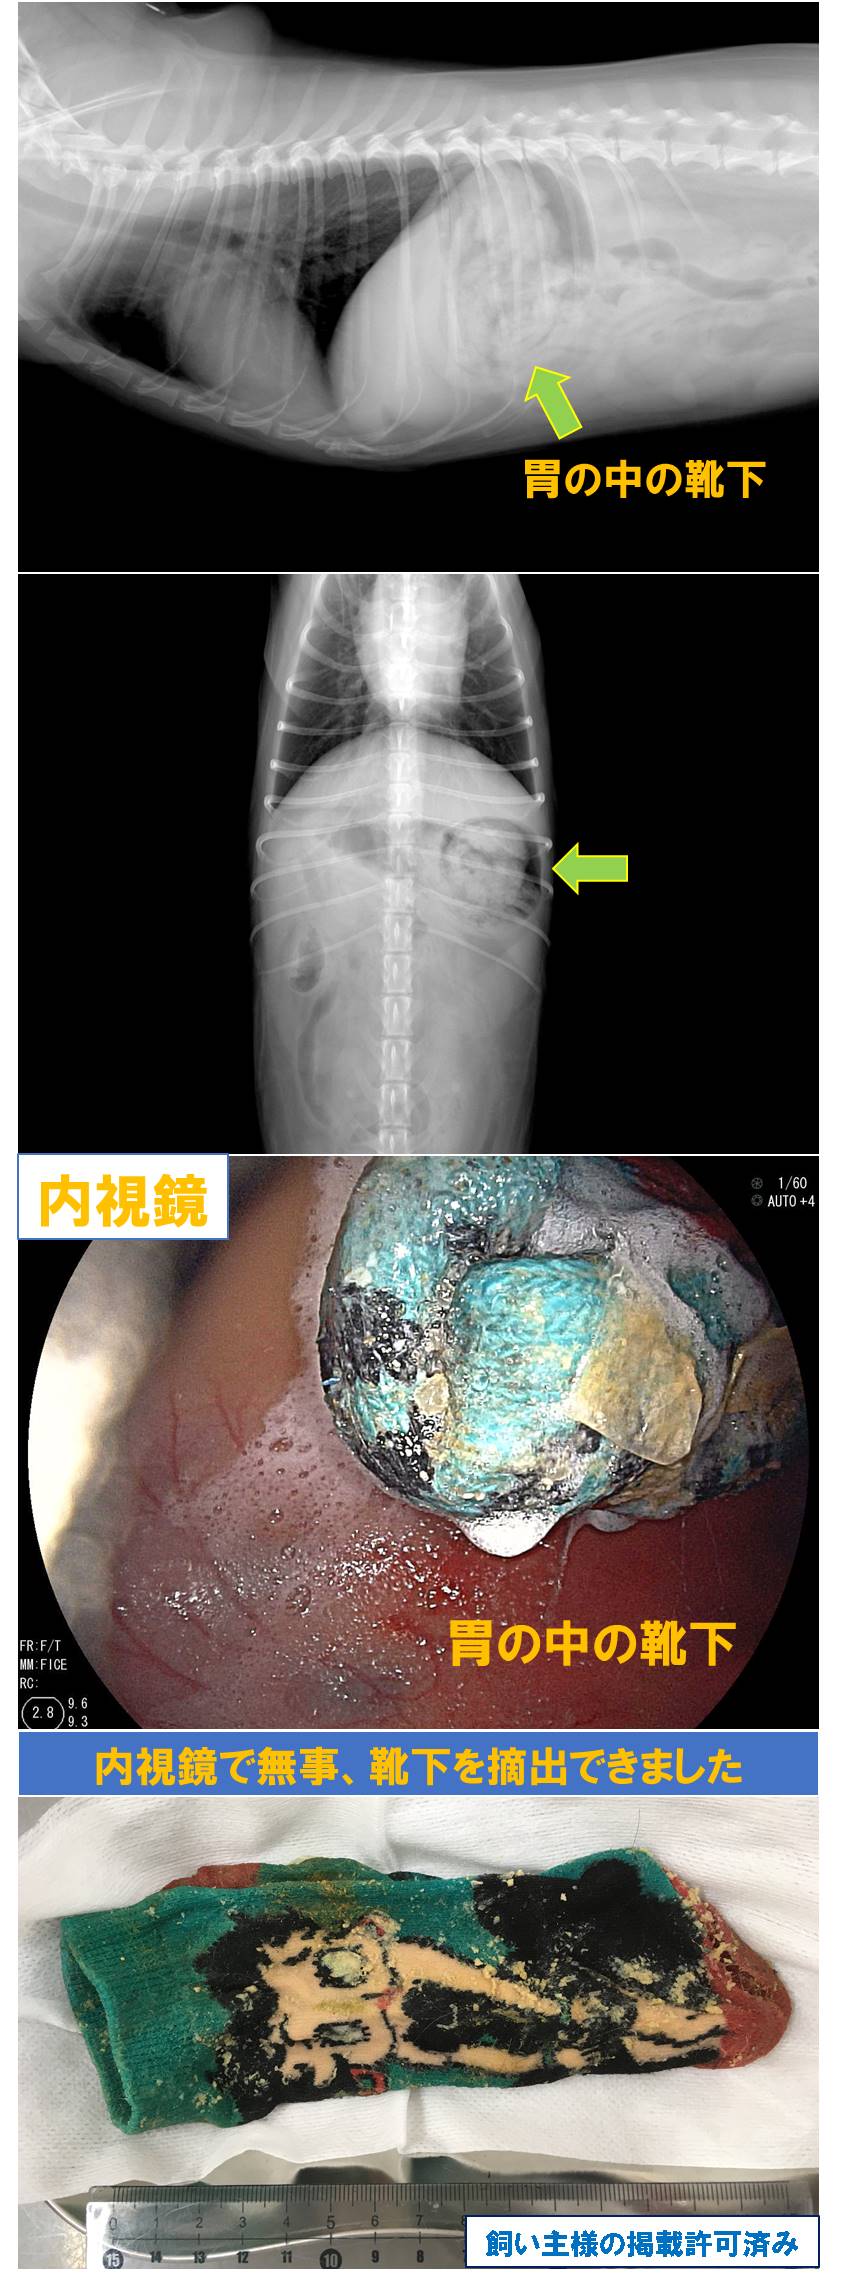

【症例3】「犬の胃内異物」

2歳 小型犬 雑種(ペキニーズ×プードル) メス

前日に靴下を誤食した。嘔吐なし。

病院で催吐処置を実施し、6回嘔吐しましたが異物はでてきませんでした。

全身麻酔をかけて内視鏡で無事靴下を摘出できました。